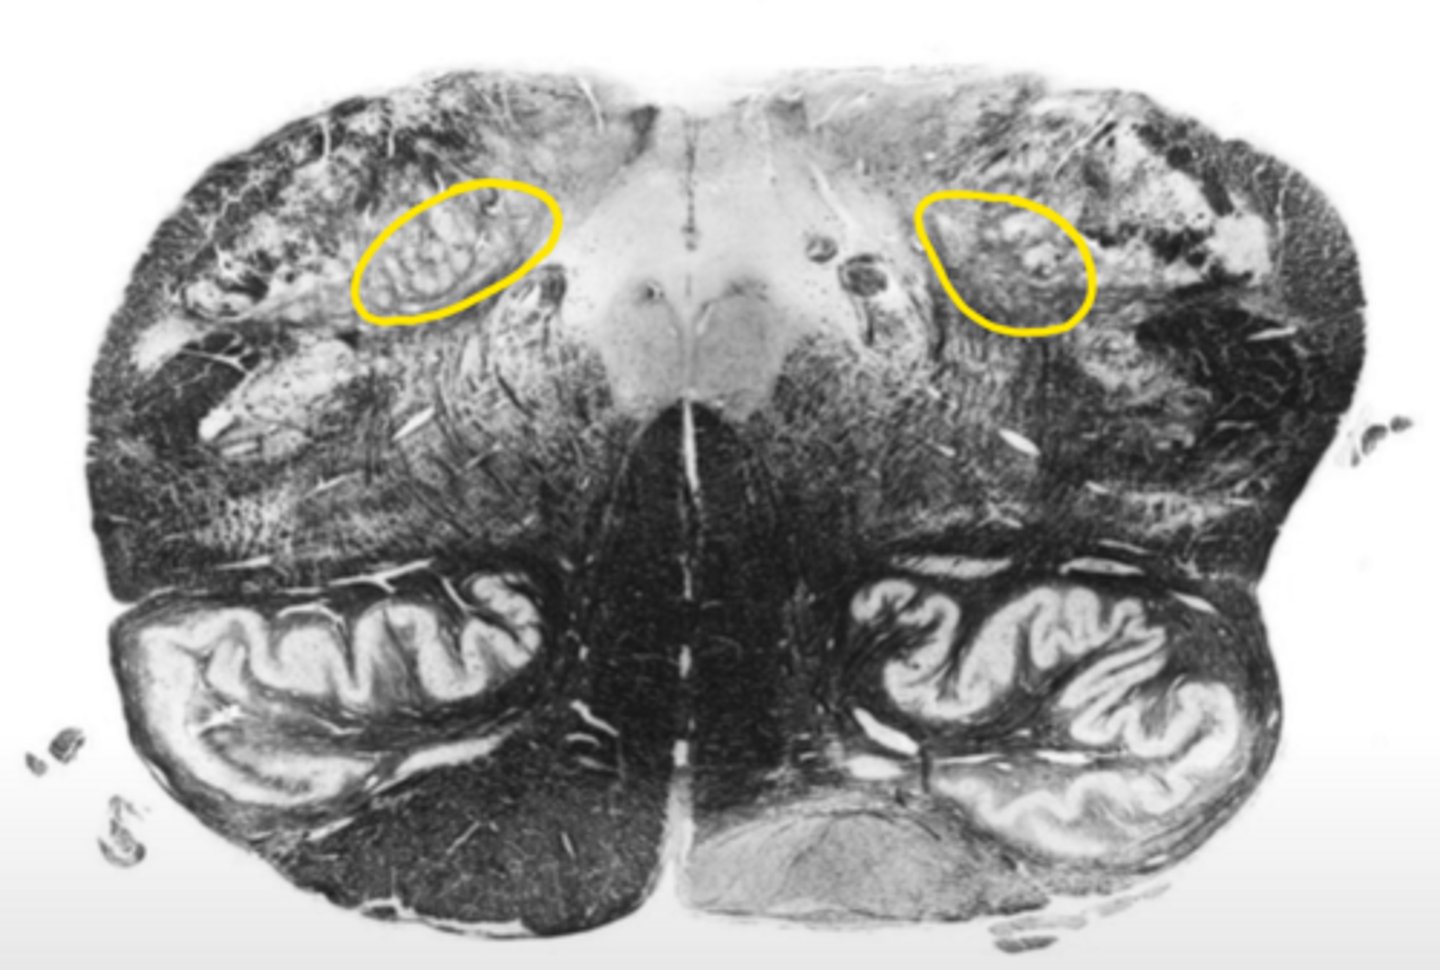

pontine nucleus

ID the nucleus

vestibular nucleus

abducens nucleus

facial nucleus

facial nerve

ID the nerve

fourth ventricle

ID the space

reticular formation

ID the structure

inferior cerebellar peduncles

olive

medial lemniscus

principle olivary nucleus

pre-olivary sulcus

corticospinal fibers

anterior median sulcus

foramen of Luschka

cochlear nucleus

glossopharyngeal nerve

open medulla

ID the brainstem level